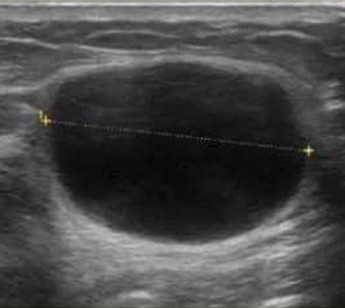

- Làm siêu âm vú. Xét nghiệm này sẽ đánh giá tính bên trong nang chứa dịch hay đặc.

Nang vú trên siêu âm. Nguồn: bci.org.au